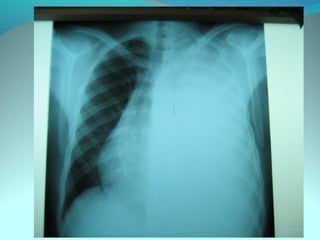

Clarté retroclaviculaire gauche d 3cm de diam

entouré d’une paroi de 1cm d’epaisseur

La limite interne se confend avec le mediastin

Les autre limites sont nette

DIAGNOSTIC

Caverne tuberculeuse gauche